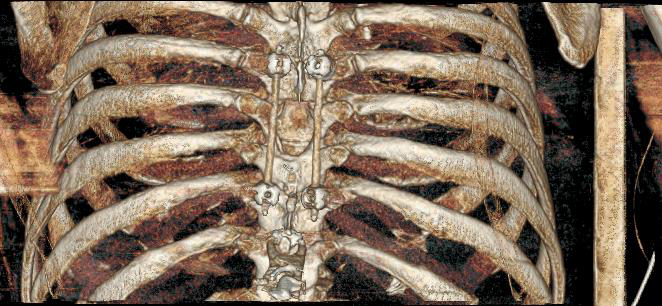

“Tumors metastasizing to the spine can weaken it,” Tran said. “Treatments for the spine tumors like surgery and radiation can further weaken the spine. We typically use titanium screws and rods to stabilize the spine. Screws made of carbon fiber, the same material used in military jets and spacecraft, provide even more strength.”

The new carbon fiber material placed in Vanacek’s back allows radiation to more effectively reach the cancer. Traditional materials are less translucent and can scatter radiation beams or shield the tumor from the radiation, thus providing a lesser dose of the needed radiation to kill the tumor.

According to Tran, the carbon fiber materials placed in Vanacek’s back will not only improve his quality of life but continue to benefit his treatment and help us better monitor any recurrence or changes in his condition.

The carbon fiber material placed in Rob's back illuminate during a recent CT scan.

“This material gives us a better way to visualize the tumor,” Tran said. “If you can detect the tumor or changes in the tumor earlier, called a recurrence, you are able to treat it earlier.”

The carbon fiber materials also allow radiation to penetrate the cancer without scattering or reflecting off the material and impacting healthy tissue.